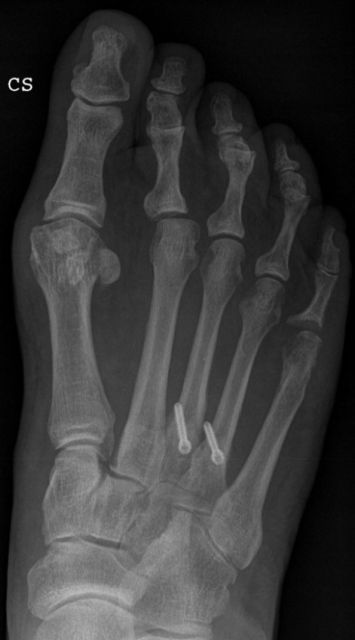

Einerseits kann eine direkte Verkürzung und damit auch Anhebung des Metatarsalköpfchens durch eine Weil-Osteotomie durchgeführt werden. Dabei wird das Grundgelenk des betroffenen Zehenstrahls eröffnet, um den Knochen zehennahe durchtrennen zu können.

Ist nur ein Zehenstrahl betroffen, bzw ist bereits eine Weil-Osteotomie durchgeführt worden, kann proximal (auf Höhe des Fußristes) eine anhebende Osteotomie vorgenommen werden (BRT-Osteotomie). Vorteil dabei ist, daß kein Gelenk eröffnet werden muß.

Die Weil-Osteotomie kann in minimalinvasiver Technik nur über Minischnitte (Stichinzisionen) durchgeführt werden. Die minimalinvasive Operationsmethode bedeutet ein sehr weichteilschonendes Verfahren, was sich in einer geringeren Schwellneigung und einem niedrigeren postoperativen Schmerzniveau äußert.